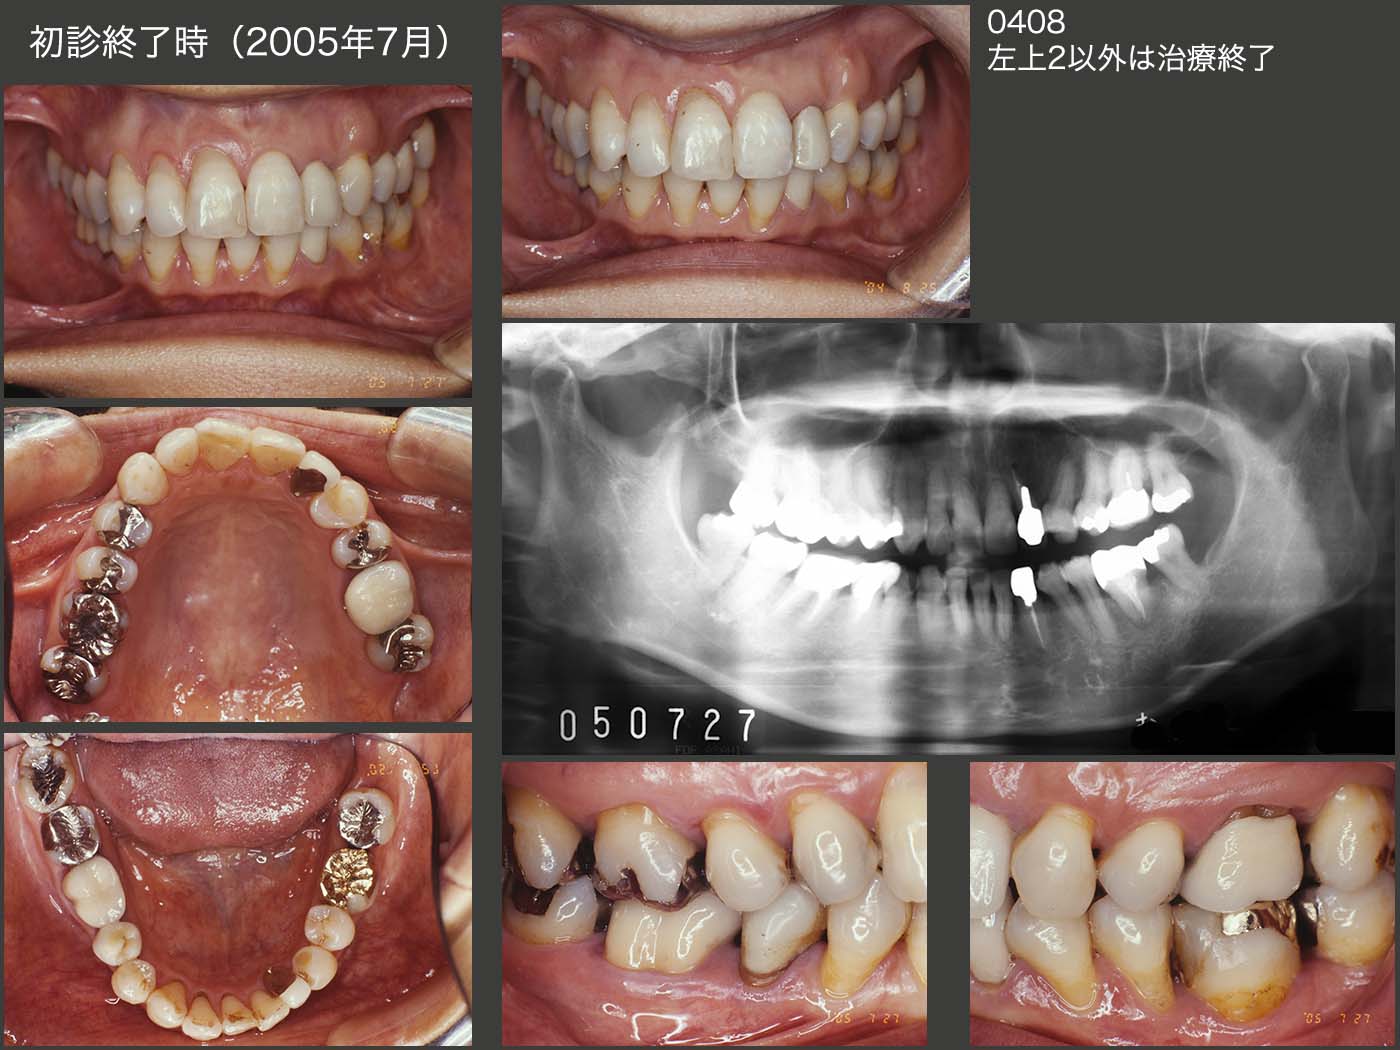

ここで,まったく恥ずかしい話であるが,左上3に犠牲になってもらい,歯科矯正まで行った左上2について,コア形成時に何と歯根を穿孔してしまった.(今なら根管内にペリオドンを貼付し,次回来院時になるべく無菌状態を維持し,止血状態を確認する.そのうえで滅菌されたダッペングラスと筆を用いたスーパーボンドにて穿孔個所を封鎖し,コアの印象採得を行っている.)当時の記録がなく,どのように処置したかの詳細は不明であるが,2004年8月,左上2には暫間被覆冠を装着し,ここ以外の治療はすべて終了した.左上2の穿孔封鎖後,約1年間経過を観察し,特に問題がみられなかったので左上2にメタルボンド冠を装着した.05年7月,すべての治療が終了した.

2007年9月のリコール時,左上2にフィステルが生じていた.穿孔部が原因であることは明らかなため,10月に抜歯し,穿孔部をスーパーボンドにて確実に封鎖し,再植した.暫く経過をみて,08年4月に再度メタルボンド冠を装着した.